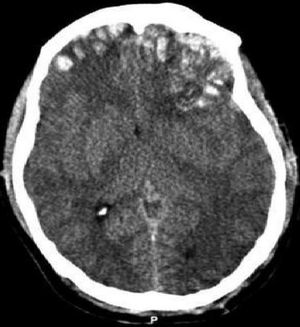

뇌좌상의 CT

산업재해나 자연재해 등 다른 요인에 의한 사고와 비교하여, 교통사고 피해자는 머리나 허리에 심한 충격을 받을 가능성이 높기 때문에 지속성 의식 장애를 비롯한 중증 후유장애가 남는 경우가 적지 않다. 또한, 뇌에 강한 충격을 받은 경우, 두부에 외상이 없더라도 고차 뇌 기능 장애에 이를 수 있다. (두부 외상, 외상성 뇌 손상 항목 참조)